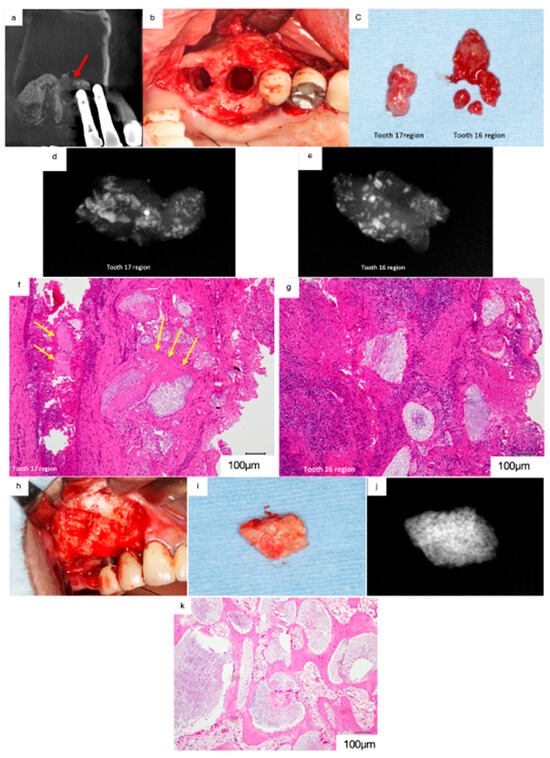

A 69-year-old male was referred to our clinic in 2016 with chief complaints of headache, nasal congestion, and postnasal discharge. He had undergone implant treatment with sinus floor elevation using Bio-Oss 10 years prior. The implants replacing 17 and 16 had been shed two months before the first visit, and the patient had developed sinusitis.

The mediodistal section of the CT image acquired at the first visit revealed prominent swelling of the sinus membrane. Pneumatic space was not observed in the maxillary sinus (Figure 9a). Radiolucent areas containing radiopaque particles were observed in the regions surrounding 17 and 16. Furthermore, artificial bone was absent at the floor of the maxillary sinus in the region surrounding 16, suggesting that the maxillary sinus was interconnected with the socket of the lost implant (Figure 9a, red arrows).

Figure 9.

(a) Mediodistal section of the CT image acquired at the first visit. Prominent swelling of the sinus membrane can be observed, and no pneumatic space is present in the maxillary sinus. Artificial bone is absent at the floor of the maxillary sinus near 16 (red arrow). (b) The soft tissues surrounding 17 and 16 were removed. (c) Artificial bone granules were observed in the removed soft tissues. (d) Radiograph of the removed soft tissues surrounding 17. Radiopaque particles of various sizes were observed in the soft tissue. (e) Radiopaque particles of various sizes can be observed in the soft tissue surrounding 16. (f) Histological decalcified specimen of the soft tissue surrounding 17 (haematoxylin and eosin staining). Bio-Oss granules can be observed among the fibrous connective tissues with moderate infiltration of inflammatory cells, and only small bone tissues remain beside the Bio-Oss granules (yellow arrows). (g) Severe infiltration of inflammatory cells was observed in the fibrous connective tissue surrounding 16, and no live bone remains around the Bio-Oss granules. (h) Bone biopsy performed on the lateral wall. (i) White particles are grossly embedded in the harvested hard tissue. (j) Radiograph of the specimen showing dense radiopaque particles in the harvested tissue. (k) The demineralised histological specimen (H.E. staining) shows that newly formed live bone is present adjacent to the Bio-Oss granules, and many foreign body giant cells can be observed around the Bio-Oss granules.

The removal of the soft tissue surrounding 17 and 16 revealed artificial bone granules (Figure 9b,c). Radiographs acquired subsequently revealed radiopaque particles of varying sizes within the tissues (Figure 9d,e). The demineralised histological specimen (H&E staining) revealed the presence of Bio-Oss granules in the fibrous connective tissues (Figure 9f,g). Moderate infiltration of inflammatory cells was observed in the fibrous connective tissues in the regions surrounding 17, and only small bone tissues were observed beside the Bio-Oss granules (Figure 9f, yellow arrows). In contrast, severe infiltration of inflammatory cells was observed in the regions surrounding 16, and no live bone was observed around the Bio-Oss granules (Figure 9g). These findings suggest that peri-implantitis disrupted osseointegration and that Bio-Oss granules were isolated from the newly formed bone tissue. Furthermore, the infection spread to the maxillary sinus through the Bio-Oss granules in the regions surrounding 16, leading to sinusitis.

A bone biopsy was performed on the lateral wall after receiving consent from the patient (Figure 9h,i). Radiographs of the harvested specimen revealed dense radiopaque particles (Figure 9j). The demineralised histological specimen (H&E staining) revealed the presence of newly formed live bone adjacent to the Bio-Oss granules (Figure 9k). Furthermore, numerous foreign body giant cells were observed around the Bio-Oss granules, suggesting that the biological reaction to the Bio-Oss granules had persisted for 10 years postoperatively. Thus, non-absorbable bone materials are associated with a risk of inducing sinusitis in patients with peri-implantitis when used as bone material for sinus floor elevation.